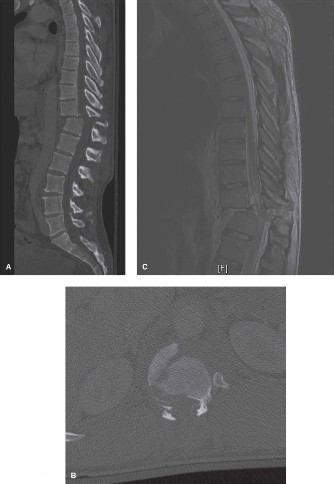

Recognize surgical and nonsurgical indications for a thoracic lymphoma? Definitively manage a thoracic lymphoma? CASE 13 A 23-year-old man was involved in a high-speed motor vehicle accident. On presentation to the trauma bay, his chief complaint was neck pain. Physical examination demonstrated that he was neurologically intact. Images of the cervical spine are shown in Figure 1–19A–B. Full workup demonstrated no other injuries.

Figure 1–19 A–B

The correct answer is (B). The imaging clearly demonstrates a Hangman’s fracture, also known as a C2 traumatic spondylolisthesis. The hallmark of this injury is a fracture through the pars interarticularis of C2, which effectively dissociates the anterior elements from the posterior arch and facet joints. A Jefferson fracture refers to C1 ring fractures that can have varying degrees of lateral displacement. There is no evidence of vertebral body comminution with posterior vertebral body involvement, which would be characteristic of a burst fracture. While some Hangman’s fractures can be associated with facet dislocation, there is no evidence of this on the imaging.

The correct answer is (B). Type I fractures have minimal horizontal displacement, no angulation, and the C2–3 disc remains intact. Type II fractures are both displaced and angulated, presumably hinging around the anterior longitudinal ligament. Importantly, these fractures reduce with longitudinal traction. Type IIA fractures have minimal horizontal displacement but are significantly angulated. It is presumed that the anterior fragment rotates in place, most likely disrupting the anterior longitudinal ligament. These injuries are worsened by traction and reduced with axial compression. Type III fractures have bilateral C2–3 facet dislocations.

The correct answer is (B). While type I fractures can be treated immediately in a hard collar, type II fractures are best treated initially with traction to achieve fracture reduction. After a short period of traction, the patient should be placed in a halo vest to allow mobilization. As indicated above, type IIA fractures should not be placed in traction; patients should be placed in a halo vest with some axial compression applied. Type III fractures require surgical reduction of the facet dislocation and internal stabilization. Objectives: Did you learn...? Identify a Hangman’s fracture based on imaging? Understand the classification of Hangman’s fractures?